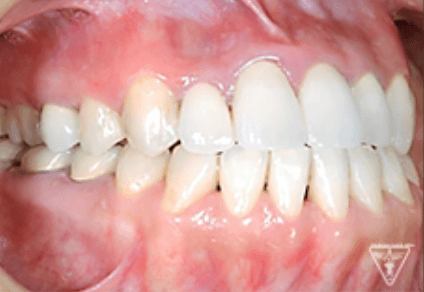

治療前

治療後